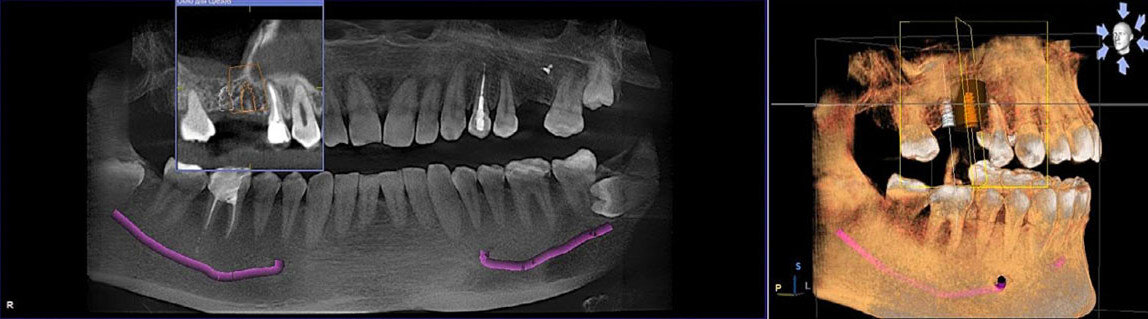

Что делать, если произошло повреждение гайморовой пазухи при установке зубных имплантов

▶Особенности строения верхнечелюстной пазухи носа Гайморова пазуха (синус) располагается в кости верхней челюсти (по одной слева и справа). Представляет собой полость объемом около 10 см кубических, внутри выстланную слизистой оболочкой. Альвеолярный верхнечелюстной отросток выступает в роли дна пазухи, за которым начинается ротовая полость. Через узкую щель синус сообщается с носовой полостью. Распространенным явлением считается воспаление гайморовых пазух. Верхушки корней боковых зубов упираются в дно синуса. Часто толщина кости между корнями и дном достигает 1 см. Иногда костная граница составляет не более 1 мм, расположение корней первого и второго моляра приводит к их проникновению в пазуху. С возрастом или по причине удаления зубов в области дна пазухи снижается плотность кости. Происходит постепенное увеличение ее размера посредством опускания дна. Возникшее при этом уменьшение высоты альвеолярного отростка становится относительным противопоказанием имплантации. ❗Риски повредить

Верхушки корней боковых зубов упираются в дно синуса. Часто толщина кости между корнями и дном достигает 1 см. Иногда костная граница составляет не более 1 мм, расположение корней первого и второго моляра приводит к их проникновению в пазуху.

С возрастом или по причине удаления зубов в области дна пазухи снижается плотность кости. Происходит постепенное увеличение ее размера посредством опускания дна. Возникшее при этом уменьшение высоты альвеолярного отростка становится относительным противопоказанием имплантации.